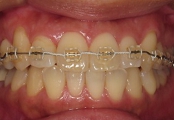

←治療前/強度な前歯の前突あり

←拡大矯正治療中.

歯列幅を,治療シュミレーションから設定した数値まで,効果的で迅速な矯正装置(緩徐拡大or急速拡大)を選択して左右的に拡大しながら,前歯の状態を整えています.

←ワイヤー矯正中

治療前と比較すると下顎は,強制的に後方に押し込まれた位置から開放されたらしく,自然に前方位を表してきました.